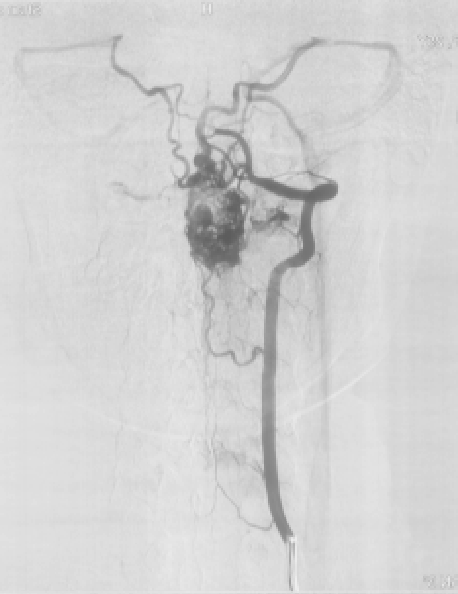

图2:术前DSA正侧位显示延髓至颈3水平畸形血管团

神经外科王贵怀主任经过认真仔细的评估后,决定进行血肿清除和畸形血管切除术,再造脊髓髓内的血流。术后由神经外科神经介入专家苏伟医师给予复查血管造影,显示畸形血管基本全切,症状明显好转,住院2周已能下地自主活动,姑娘愁苦的脸上终于露出了笑容。